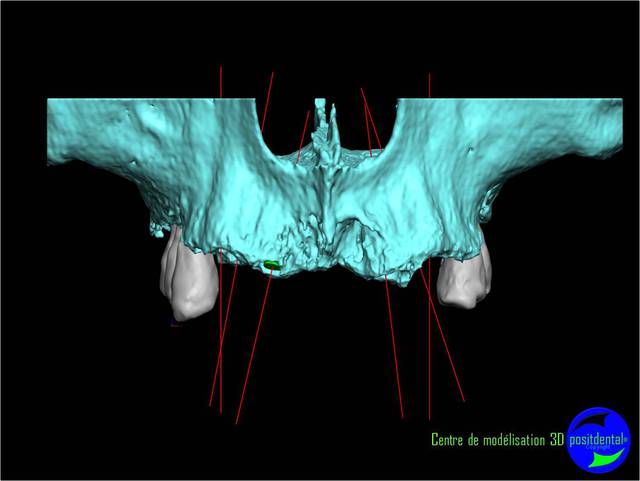

La vidéo présente à partir des plans de traitements, des chirurgies de beotien , des dispositifs médicaux sur mesure positdental et positguide la mise en charge immédiate post-extractionnelle d’un bridge provisoire à armature métal en prothèse fixe sur implants cône morse donc sans vis de maintien. Une question est émise « comment obtient-on ce résultat ? ». Une partie des réponses comme la prédictibilité, la reproductibilité peuvent y être déduite pour d’autre il faudra la bonté de beotien de faire partager les résultats clinique.il nous fait la générosité de poster la phase cicatriciel à 7 jours et des photos de la chirurgie sur un cas.

planif cas 1

Si tu as suivi les cas présentés depuis plusieurs années les bridges provisoires ont une armature métal pour la rigidité du fixateur externe, l’intervention se déroule en 1 seul temps chirurgical donc sans prise d’empreinte, c’est pour cela que je parle de MCI. Pour la passivité du bridge avec le système Nobel Guide et leurs piliers expansifs je n’ai vue aucun cas clinique présenté sur le forum. As-tu déjà utilisé le procédé ? Dans les cas présentés sur la vidéo, aucune clé de positionnement n’a été utilisée, le placement des piliers se fait selon la simulation implantaire assistée par ordinateur, leurs présentations a été faite en prospective par OTP, modèle 3D et à la demande de beotien la solution pilier fixe a été retenu à la place du bridge transvisé. Quel sont les compléments d’information que tu as besoin et ou la photo ne te suffi pas ? Pour le protocole d’une MCI, empreintes des maxillaires, dimension verticale de l’occlusion, définition de l’esthétique souhaitée, prescriptions, réalisation du Positscan, traitement des informations à partir des données DICOM, simulation implantaire assistée par ordinateur, validation, réception des DMSM selon les types d’implants et encastillages les procédures varient. Quel système implantaire utilise-tu ?